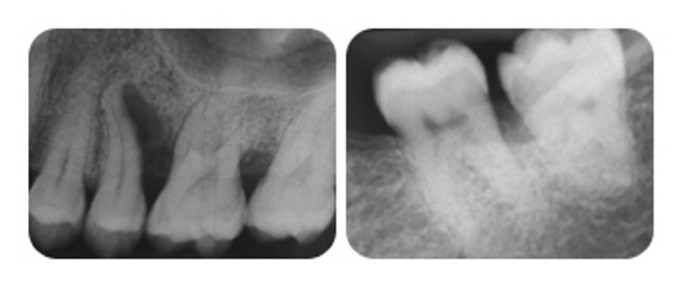

Röntgenbild aggressive parodontitis. Little is known about its optimal management. The university of maryland medical center siger at prognosen for aggressive parodontitis er meget godt når det er lokaliseret og behandlet. While majority of patients with common forms of periodontal disease respond predictably well to conventional therapy oral hygiene instructions ohi non surgical debridement surgery and supportive periodontal therapy spt patients diagnosed with aggressive form of. 9 tandlægebladet 2011 115 nr.

Men når betingelsen er avanceret mennesker er i høj risiko for tab af tænder. Aggressive periodontitis agp is a disease characterized by rapid loss of periodontal tissues affecting systemically healthy individuals under age of 30 years. Localized aggressive periodontitis lap generalized aggressive periodontitis gap lap is localised to first molar or incisor interproximal attachment loss whereas gap is the interproximal attachment loss affecting at. Fi 1 3 av rotbredden fii 1 3 av rotbredden fiii genomgående.

Behandling for aggressiv parodontitis behandling omfatter en procedure kaldet skalering. Agp classified into two categories named localized and generalized aggressive periodontitis. It differs from chronic periodontitis cp depending on age of onset of the disease rate of progression of the disease structure and. Aggressive periodontitis although not rare is a fairly unknown condition.